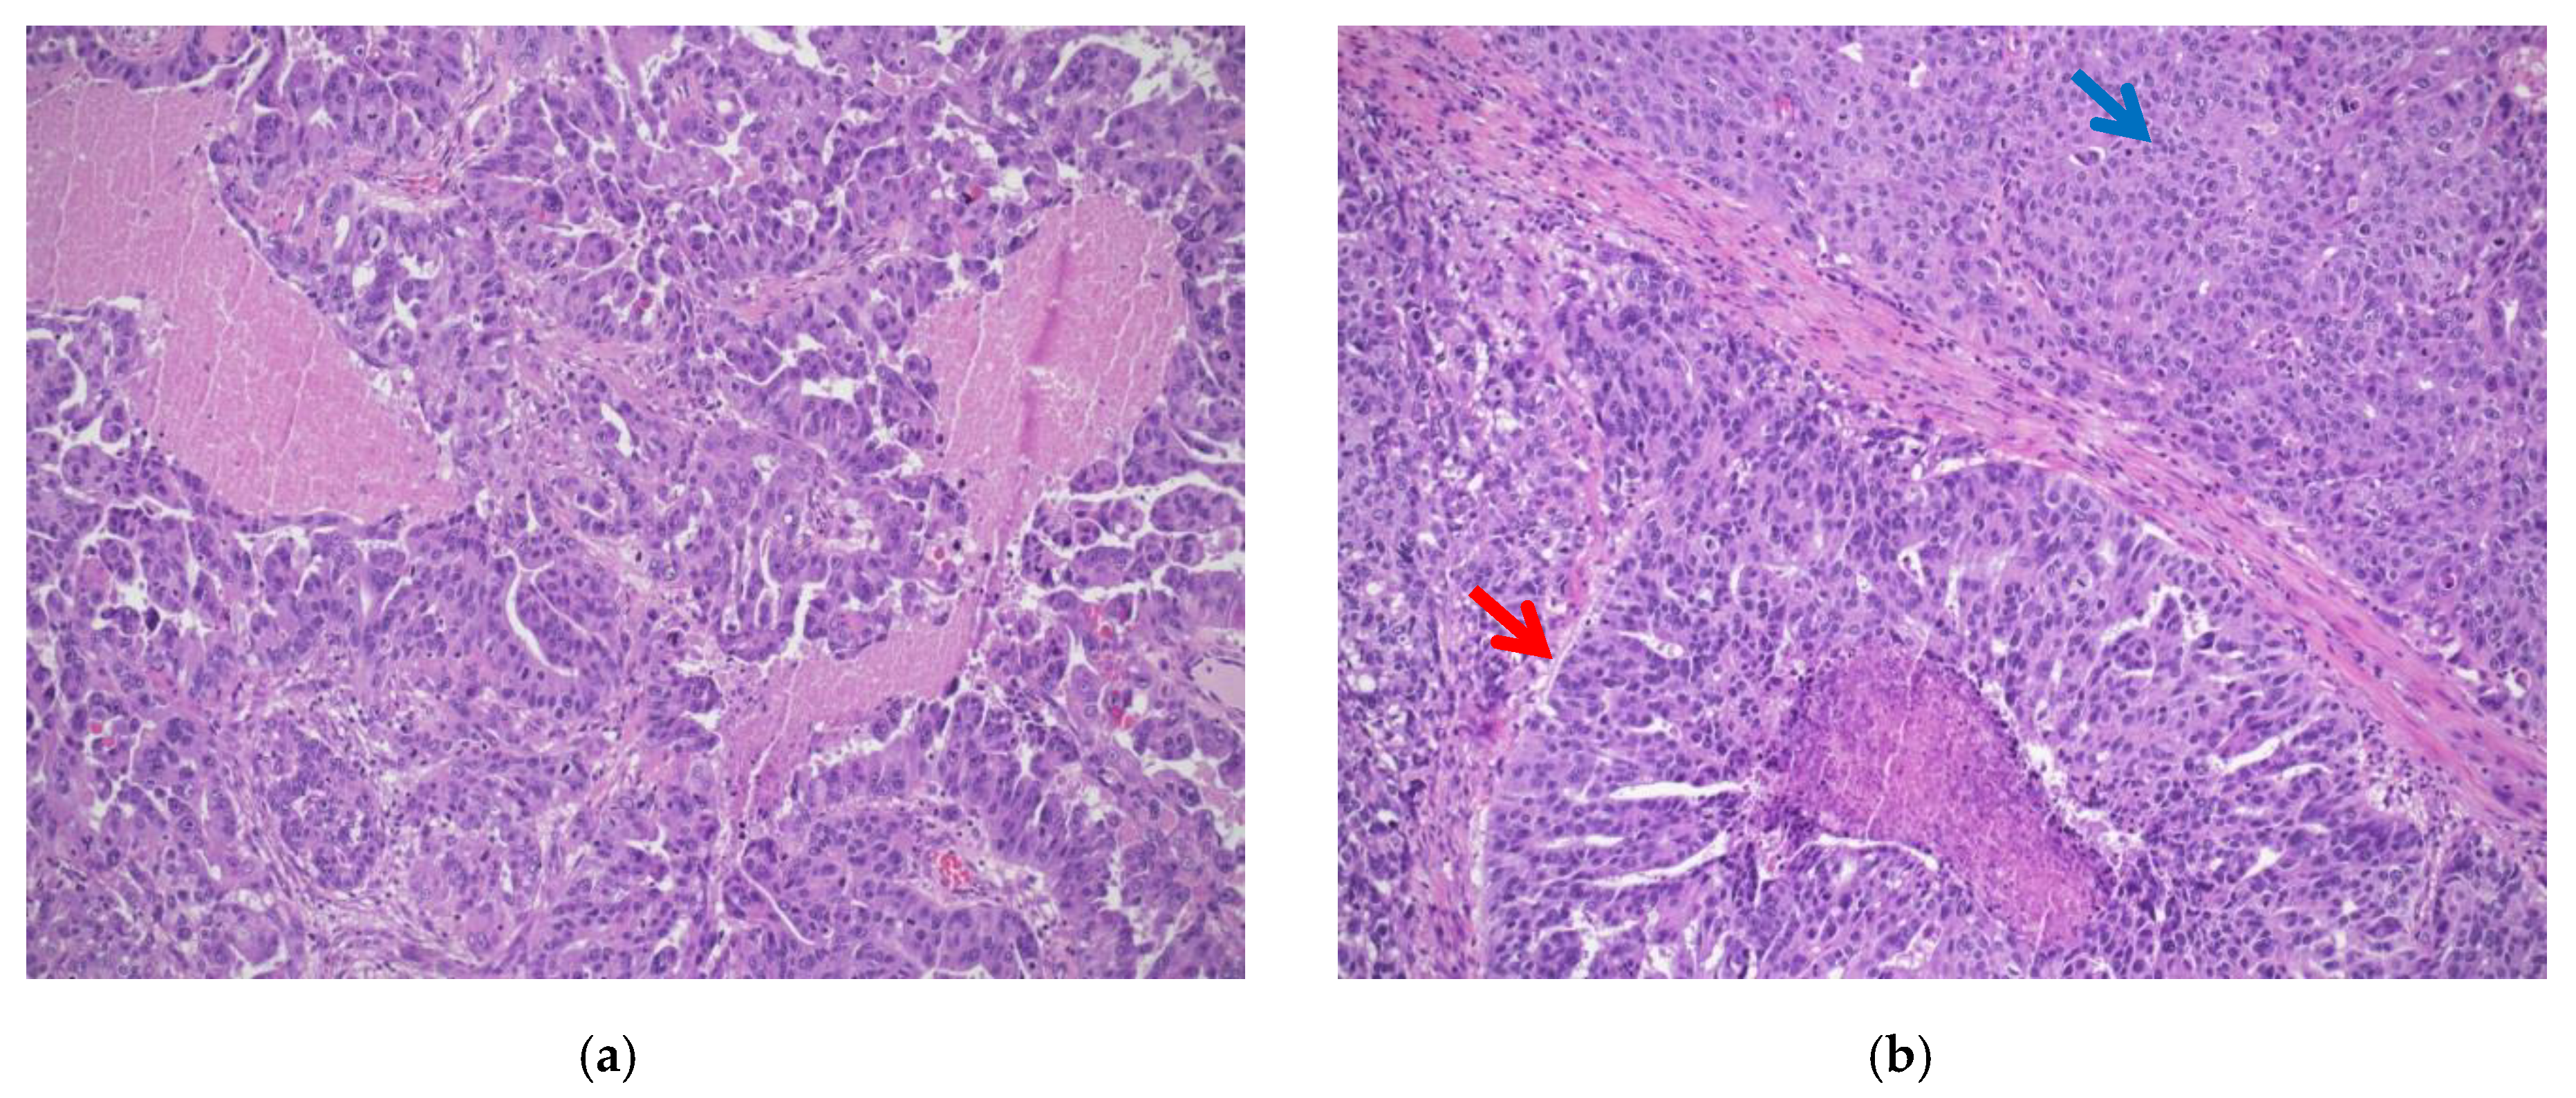

- Classic histotype: characterized by a papillary, micropapillary, and/or solid architecture, marked nuclear pleomorphism and high mitotic index (Figure 1a).

- “SET” variant (solid-pseudoendometrioid and transitional): characterized by an admixture of solid, glandular/endometrioid-like, and transitional/malignant Brenner-like growth patterns), higher mitotic index compared to the classic histotype, and a high number of tumor-infiltrating lymphocytes (TILs) (Figure 1b). In 2012, a study from Soslow et al. demonstrated a statistical association between BRCA1/2 mutation and SET morphology [12]